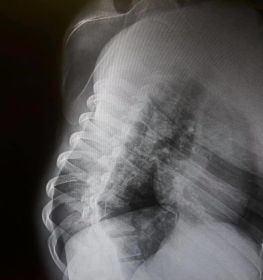

Omurga eğriliği yaşan insanlarda eğer eğrilik 40 dereceyi aşmış ise cerrahi operasyon ile tadavi edilir. Bu şekilde bir tedavi çok riskli ve zordur. Ardından ise mutlaka fizik tedavi ek olarak da korse tedavisi uygulanmalıdır.

Skolyoz hastalığı omurgaların dizilimindeki düzensizlik ve yamukluktur. Çoğunlukla çocuklukta görülen hastalık yetişkinlerde de az da olsa görülebilir. Sağa sola omurgalardaki çıkıntıların zamanla omurilik eğriliği bir hale getirdiği hastalıkta erken tanı çok önemlidir. İster yetişkin isterse çocuk olsun erken teşhis sonucunda fizik tedavi yöntemi işe yarar. Hastalık özellikle kişilerin günlük yaşantılarını etkileyen olumsuzluklar yaşatan ve yaşam kalitesini düşüren bir rahatsızlıktır. Geç kalınmadan tedaviye başlanmalıdır.